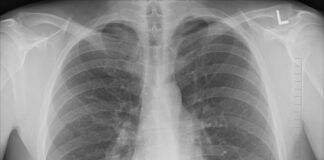

Jak wyglądają płuca biernego palacza?

Palenie tytoniu jest jednym z największych zagrożeń dla zdrowia publicznego na całym świecie. Nie tylko osoby, które same palą, są...